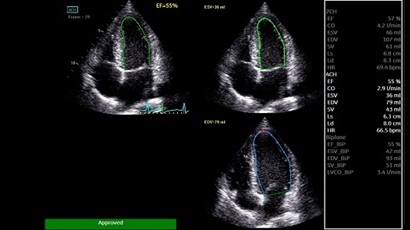

AUTO 2D EF:

Да

AFI:

Q-ANALYSIS:

ADVQSCAN:

TDI:

LVO Contrast:

• AUTO 2D EF - режим автоматической недопплеровской количественной оценки глобальной сократительной функции ЛЖ (по Simpson).

• AFI - режим цифровой недопплеровской качественной и количественной оценки региональной сократительной функции ЛЖ.

• LVO CONTRAST - опция контрастирования полости левого желудочка.